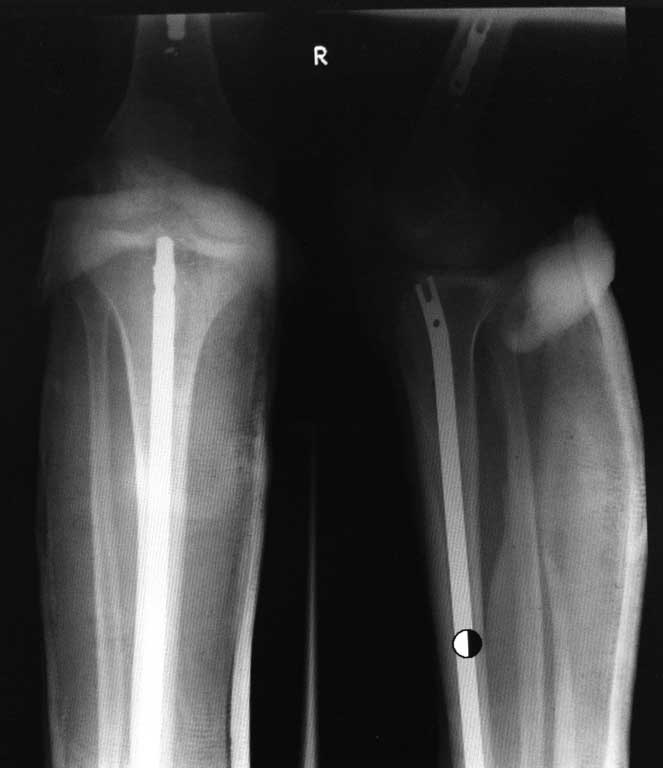

[Ortho] Несращение дистального отдела костей голени

И еще снимок в/3 голени: